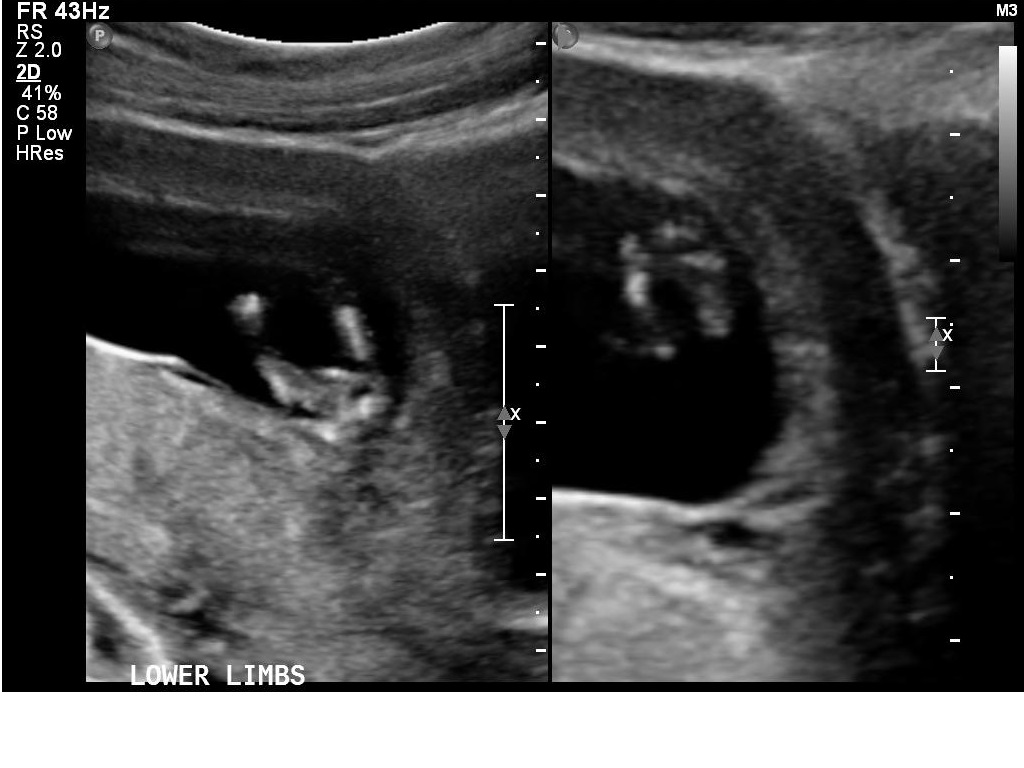

I had my 12w1d ultrasound today, but baby measured ahead at 13 weeks. Bub was very uncooperative and made it hard for the technician to get the NT measurements, which was good in a way because I got to see lots of bub! We got heaps of pictures and I will upload a few here.

I *think* I can tell the gender by the nub pictures but I'd love lots of guesses!!

What do you all think?